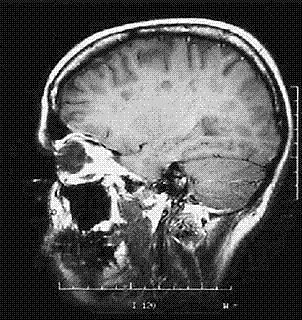

Ad oggi, sono stati portati a termine due studi sul trattamento endovascolare della CCSVI come terapia della sclerosi multipla iniziati dalla constatazione della della presenza di malformazioni

anatomiche in alcune vene giugulari di malati di SM, in grado di ostacolare il passaggio del sangue verso cervello e midollo spinale. Zamboni e colleghi hanno trattato tali volontari con